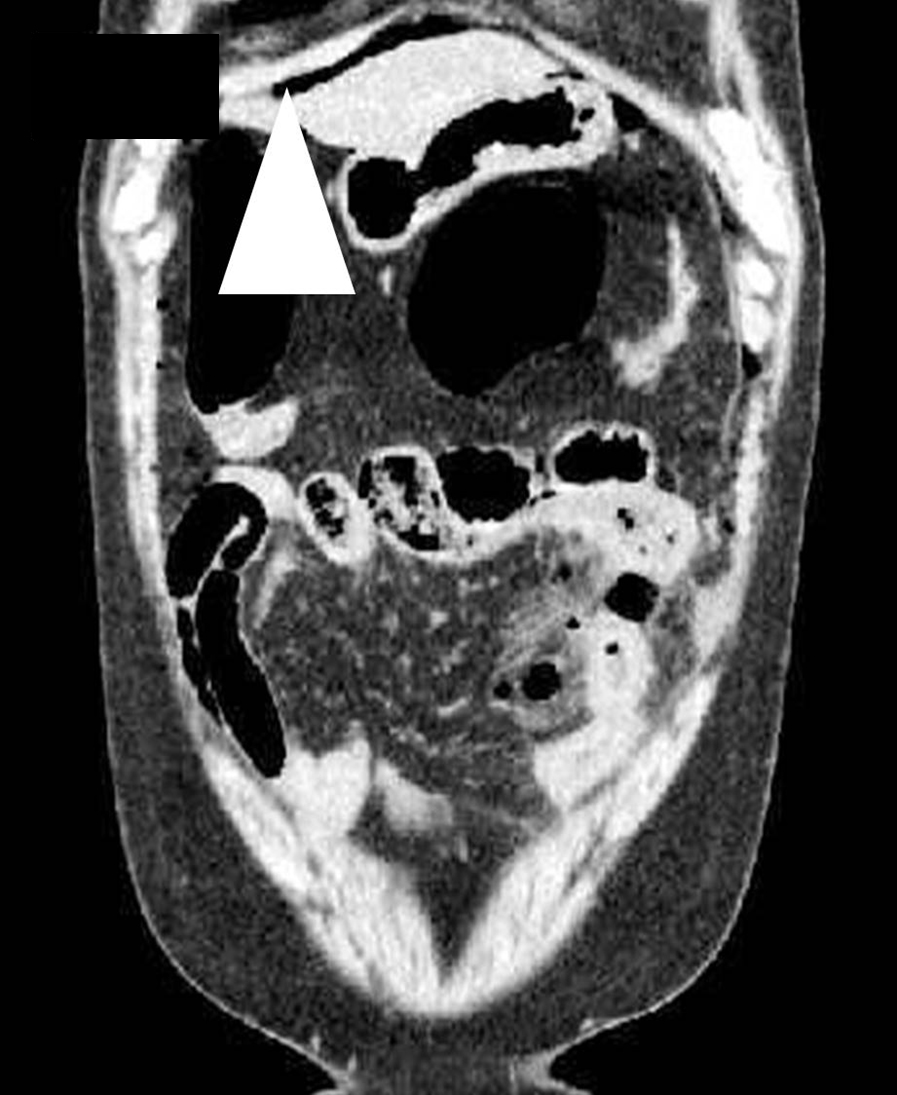

腹部CT所見:右横隔膜下,網囊腔を中心に多量の遊離ガスが散在し,左側小腸に軽度拡張と壁浮腫があり,周囲脂肪織の濃度上昇と少量の液貯留を伴っており,同部の穿孔,腹膜炎が疑われた.ダグラス窩には少量の腹水があり,大腸は大半が虚脱しており,明らかな異常所見は認めず,肝内に腫瘍性病変は認めなかった(Fig. 1).

Enhanced CT showed free air in the right subphrenic space (arrowhead) and omental bursa.